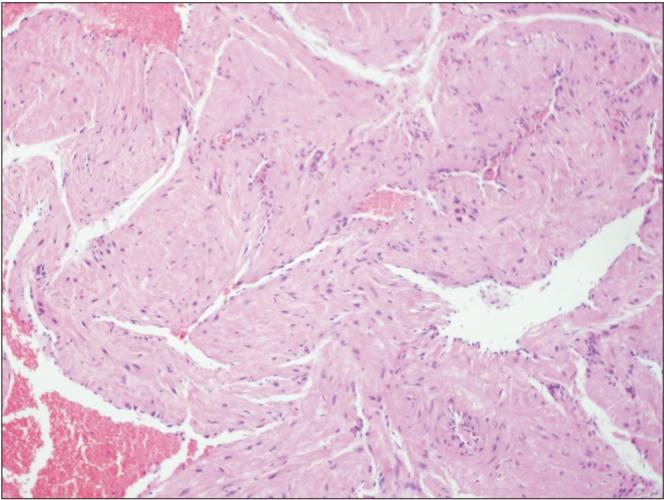

This study presents a case of an oral angioleiomyoma along with its clinical diagnostic approach and laboratory confirmation. The differential diagnosis, especially from angioleiomyosarcoma, is also included. A 51-year-old patient presented with a tumor-like lesion on his upper labial mucosa. The clinical examination revealed a benign lesion that was surgically removed. Histopathological and immunohistochemical examinations confirmed the diagnosis of an oral angioleiomyoma. The post-surgical period was uneventful. No recurrence had occurred after a year of follow-up surveillance. Oral angioleiomyoma is a very rarely occurring oral lesion. Clinically, it may mimic some benign lesions, including fibroma, pyogenic granuloma or minor salivary gland tumor. Surgical excision is the treatment of choice. Histological and immunohistochemical examination can confirm the diagnosis. The differential diagnosis is crucial to rule out angioleiomyosarcoma.

本研究报告了一例口腔血管平滑肌瘤病例及其临床诊断方法和实验室确诊情况。文中还包括了鉴别诊断,特别是与血管平滑肌肉瘤的鉴别。一名51岁患者上唇黏膜出现肿瘤样病变。临床检查显示为良性病变,遂进行手术切除。组织病理学和免疫组织化学检查确诊为口腔血管平滑肌瘤。术后恢复顺利。随访一年未出现复发。口腔血管平滑肌瘤是一种非常罕见的口腔病变。临床上,它可能类似一些良性病变,包括纤维瘤、化脓性肉芽肿或小涎腺肿瘤。手术切除是首选治疗方法。组织学和免疫组织化学检查可确诊。鉴别诊断对于排除血管平滑肌肉瘤至关重要。